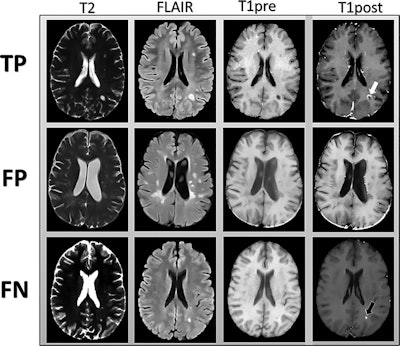

MR images are examples of T2-weighted, fluid-attenuated inversion-recovery (FLAIR), and precontrast T1-weighted images input into the deep-learning model. Postcontrast T1-weighted images (T1post) demonstrate areas of true-positive (white arrow) and false-negative (black arrow) enhancement. FN = false-negative classification of enhancement, FP = false-positive classification of enhancement, TP = true-positive classification of enhancement. Images courtesy of Radiology.Their deep-learning approach achieved a sensitivity of 78% (± 4%) and specificity of 73% (± 2.7) averaged across the five test sets for predicting contrast enhancement in each MRI slice. In addition, sensitivity was 72% (± 9%) and specificity was 70% (± 6%) in determining the presence of any enhancing lesions in an MS patient.